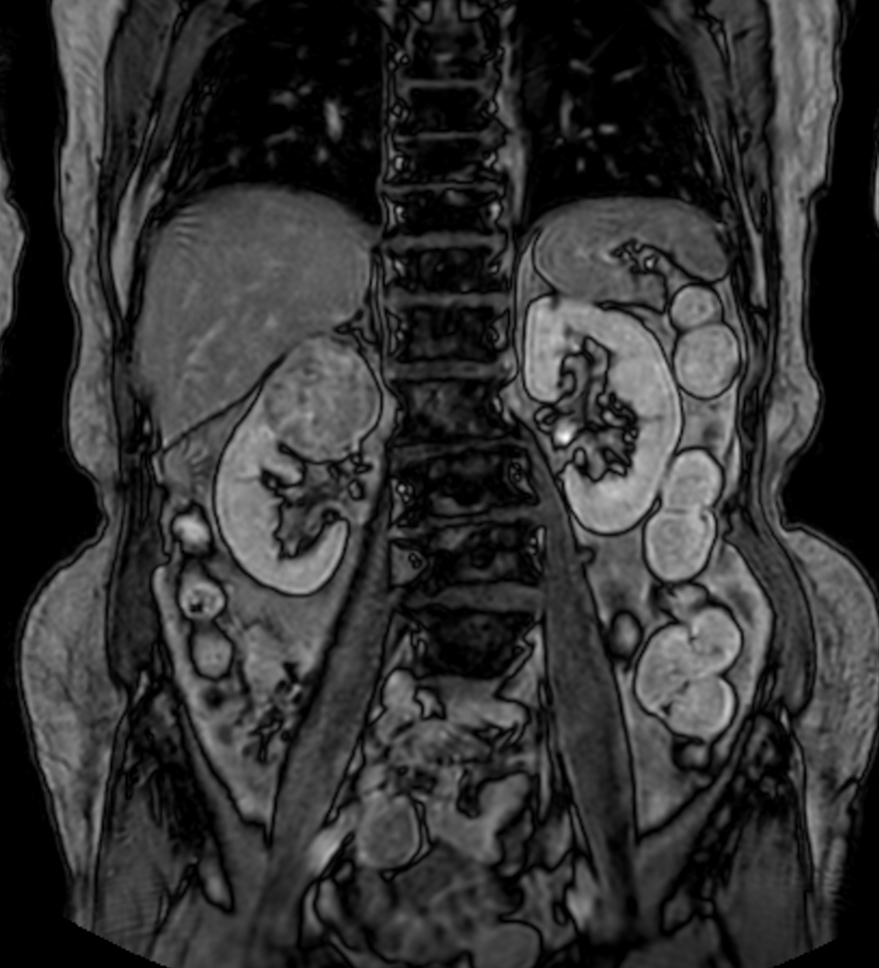

Patient with a kidney lesion. The ExamCard includes techniques for 3D imaging (PelvisVIEW, eTHRIVE) allowing for multiple image directions in one single scan, efficient fat-free imaging over large field-of-views (mDIXON XD), a multi-phase contrast-enhanced sequence (4D FreeBreathing) to improve imaging confidence and Compressed SENSE to accelerate the entire exam.

T2w TSE